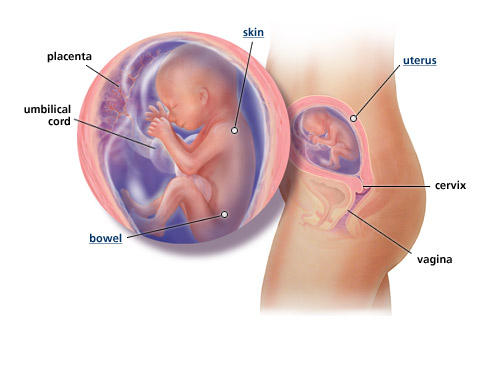

Двадцятий тиждень завершує п'ятий місяць і є серединою вагітності. Організм дитини на даному етапі розвитку вже сформований настільки, що через 3-4 тижні в екстрених випадках він зможе вижити поза материнського тіла. Але в нормі він ще 4 місяці перебуватиме під його захистом.

Вага плоду на 20 тижні становить близько 340 г, розмір - не більше 25 см. Він має повністю сформованими зоровими органами, тому все більш активно реагує на світлові подразники - яскраве світло, світлові спалахи.

До закінчення 20 тижнів він має майже до кінця сформувався шкірний покрив. На його шкірі з'являються численні складки. У цей період часу активно формуються легкі, у плода вже працює кишечник. У кишечнику формується меконий, що представляє собою зелену масу, яка містить відходи його організму.

В середині вагітності організм дитини практично повністю сформувався. Йому необхідно трохи підрости для появи на світ. На даному етапі розвитку дитина має рухливу міміку. Мимоволі він морщить ніс, робить різні гримаси, які чітко видно при УЗД.

УЗД на 20 тижні відрізняється тим, що в процесі його проведення фахівець може оцінити стан внутрішніх органів і систем організму дитини. Він уважно досліджує його серцево-судинну систему, нирки, хребет. Саме на даному терміні вагітності зазвичай діагностуються патології серця. УЗД дозволяє встановити діагноз вродженої вади серця ще на етапі внутрішньоутробного розвитку майбутньої дитини.

УЗД з метою визначення розміру плоду носить назву фетометрії. Воно має на увазі встановлення точного розміру тіла дитини і окремо взятих його структур: окружності голови і живота, довжину стегна, куприка-тім'яної розмір і т.д. Фетометрія плода на 20 тижні дозволяє визначити, чи правильно розвиваються структури його тіла відносно один одного, визначити наявність відхилень в їх розвитку.